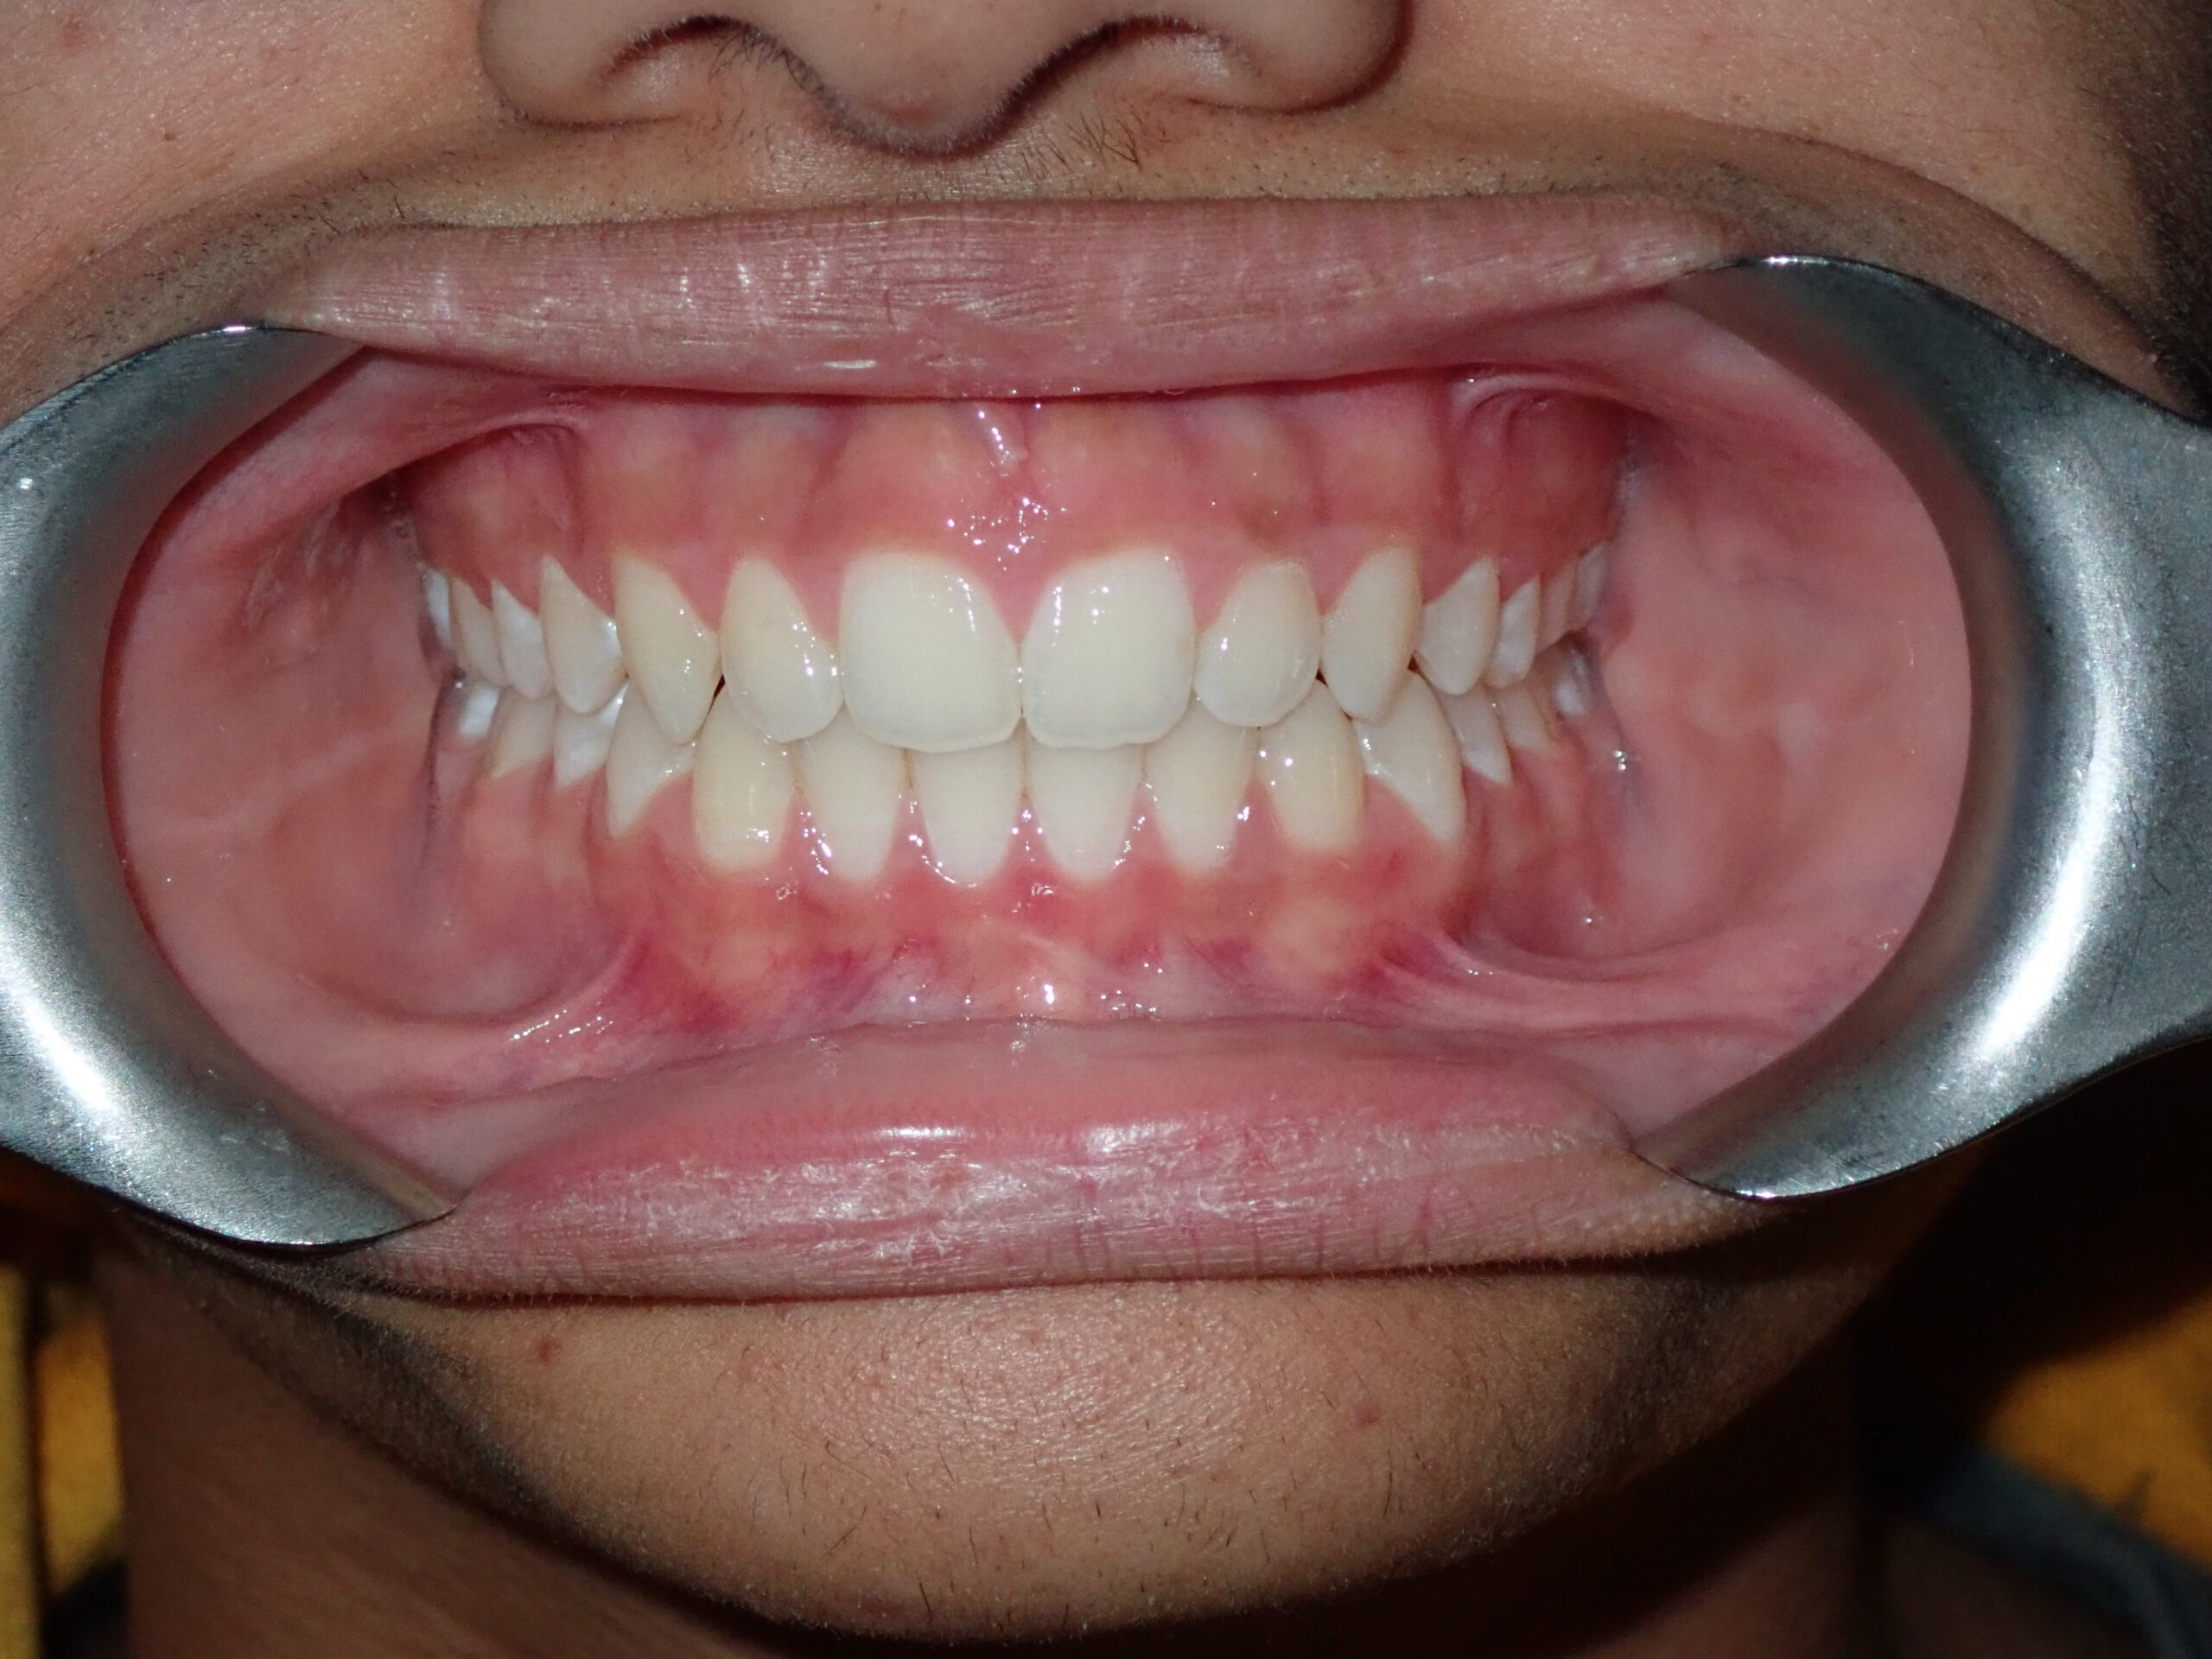

Patient Resultsنتائج المرضى

Real Results. Real Patients.نتائج حقيقية. مرضى حقيقيون.